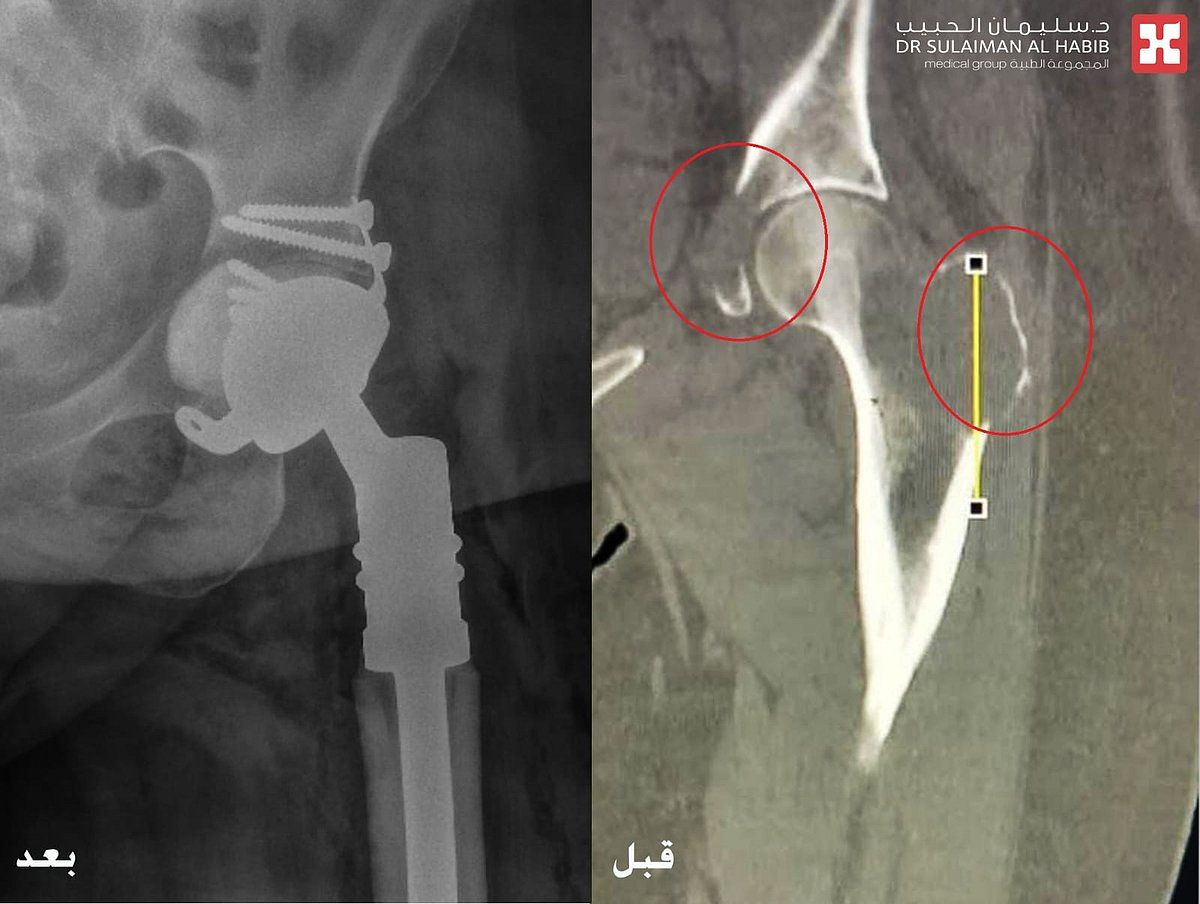

والذي أضاف بأنه عند وصول المراجعة للعيادة، تم الإستماع إلى شكواها والإطلاع على تاريخها المرضي وإجراء الفحص السريري، وتبين معاناتها من صعوبة المشي والحركة والشعور بنوبات من الألم خاصة وقت النوم أو الرغبة بالمشي، وظهور كتلة ورمية بالفخذ. على الفور تم إخضاعها لفحوصات طبية دقيقة بالتصوير المقطعي C.T Scan والأشعة السينية الرقمية Digital X-Rays والتحاليل المخبرية.

مشيراً إلى أن نتائج الفحوصات كشفت عن وجود ورم خبيث منتشر في عظمة الفخذ والحوض، نتج عنه حدوث تفتت للعظم في تلك المنطقة. مفيداُ بأنه تم تكوين فريق طبي من استشاري جراحة العظام والأورام والتخدير والعناية المركزة، وعقب دراستهم لكامل نتائج الفحوصات، تم اتخاذ القرار بالتدخل الجراحي العاجل ووضع خطة علاجية دقيقة، وذلك للحيلولة دون إصابة المراجعة بمزيد من الأعراض والمضاعفات الحادة، والمتمثلة في كبر حجم الورم وانتشاره في مواضع أخرى بالجسم.

موضحاً بأنه إخضاع المراجعة لجراحة دقيقة استغرقت 4 ساعات متواصلة تحت التخدير العام، وتم فيها استئصال الورم السرطاني وإزالة عظمة الفخذ المتضررة، ومن ثم عمل ترميم للمنطقة المصابة، تبع ذلك زراعة مفصل صناعي من نوع خاص، نقلت بعدها إلى جناح التنويم.